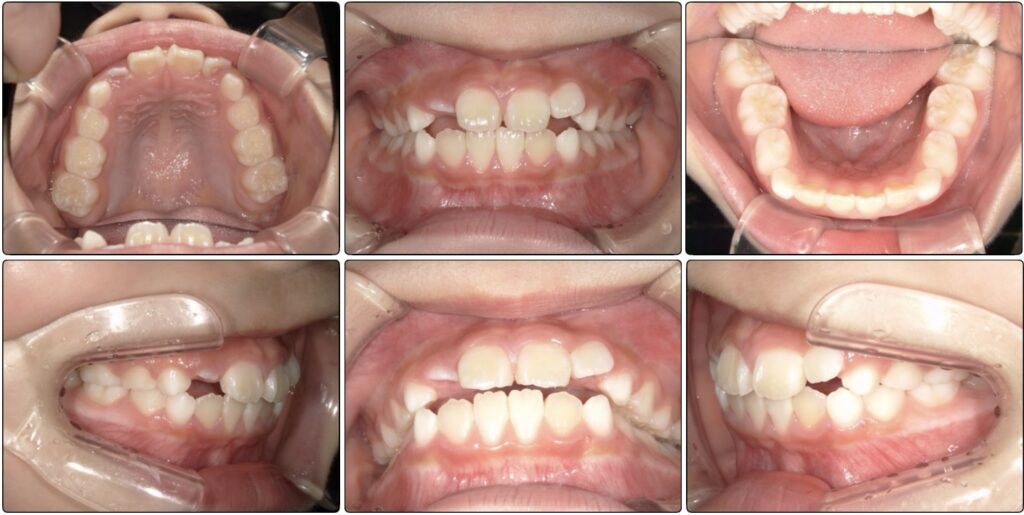

治療前 / 現在

治療開始時

現在

初診の写真を見ると前歯はある程度並んでいますが2番目の歯は斜めに生えており下からの写真では丸いアーチというより平坦のアーチになっています。

これは歯が大きいからよりも顎が小さくスペースが足りていないケースがほとんどです。